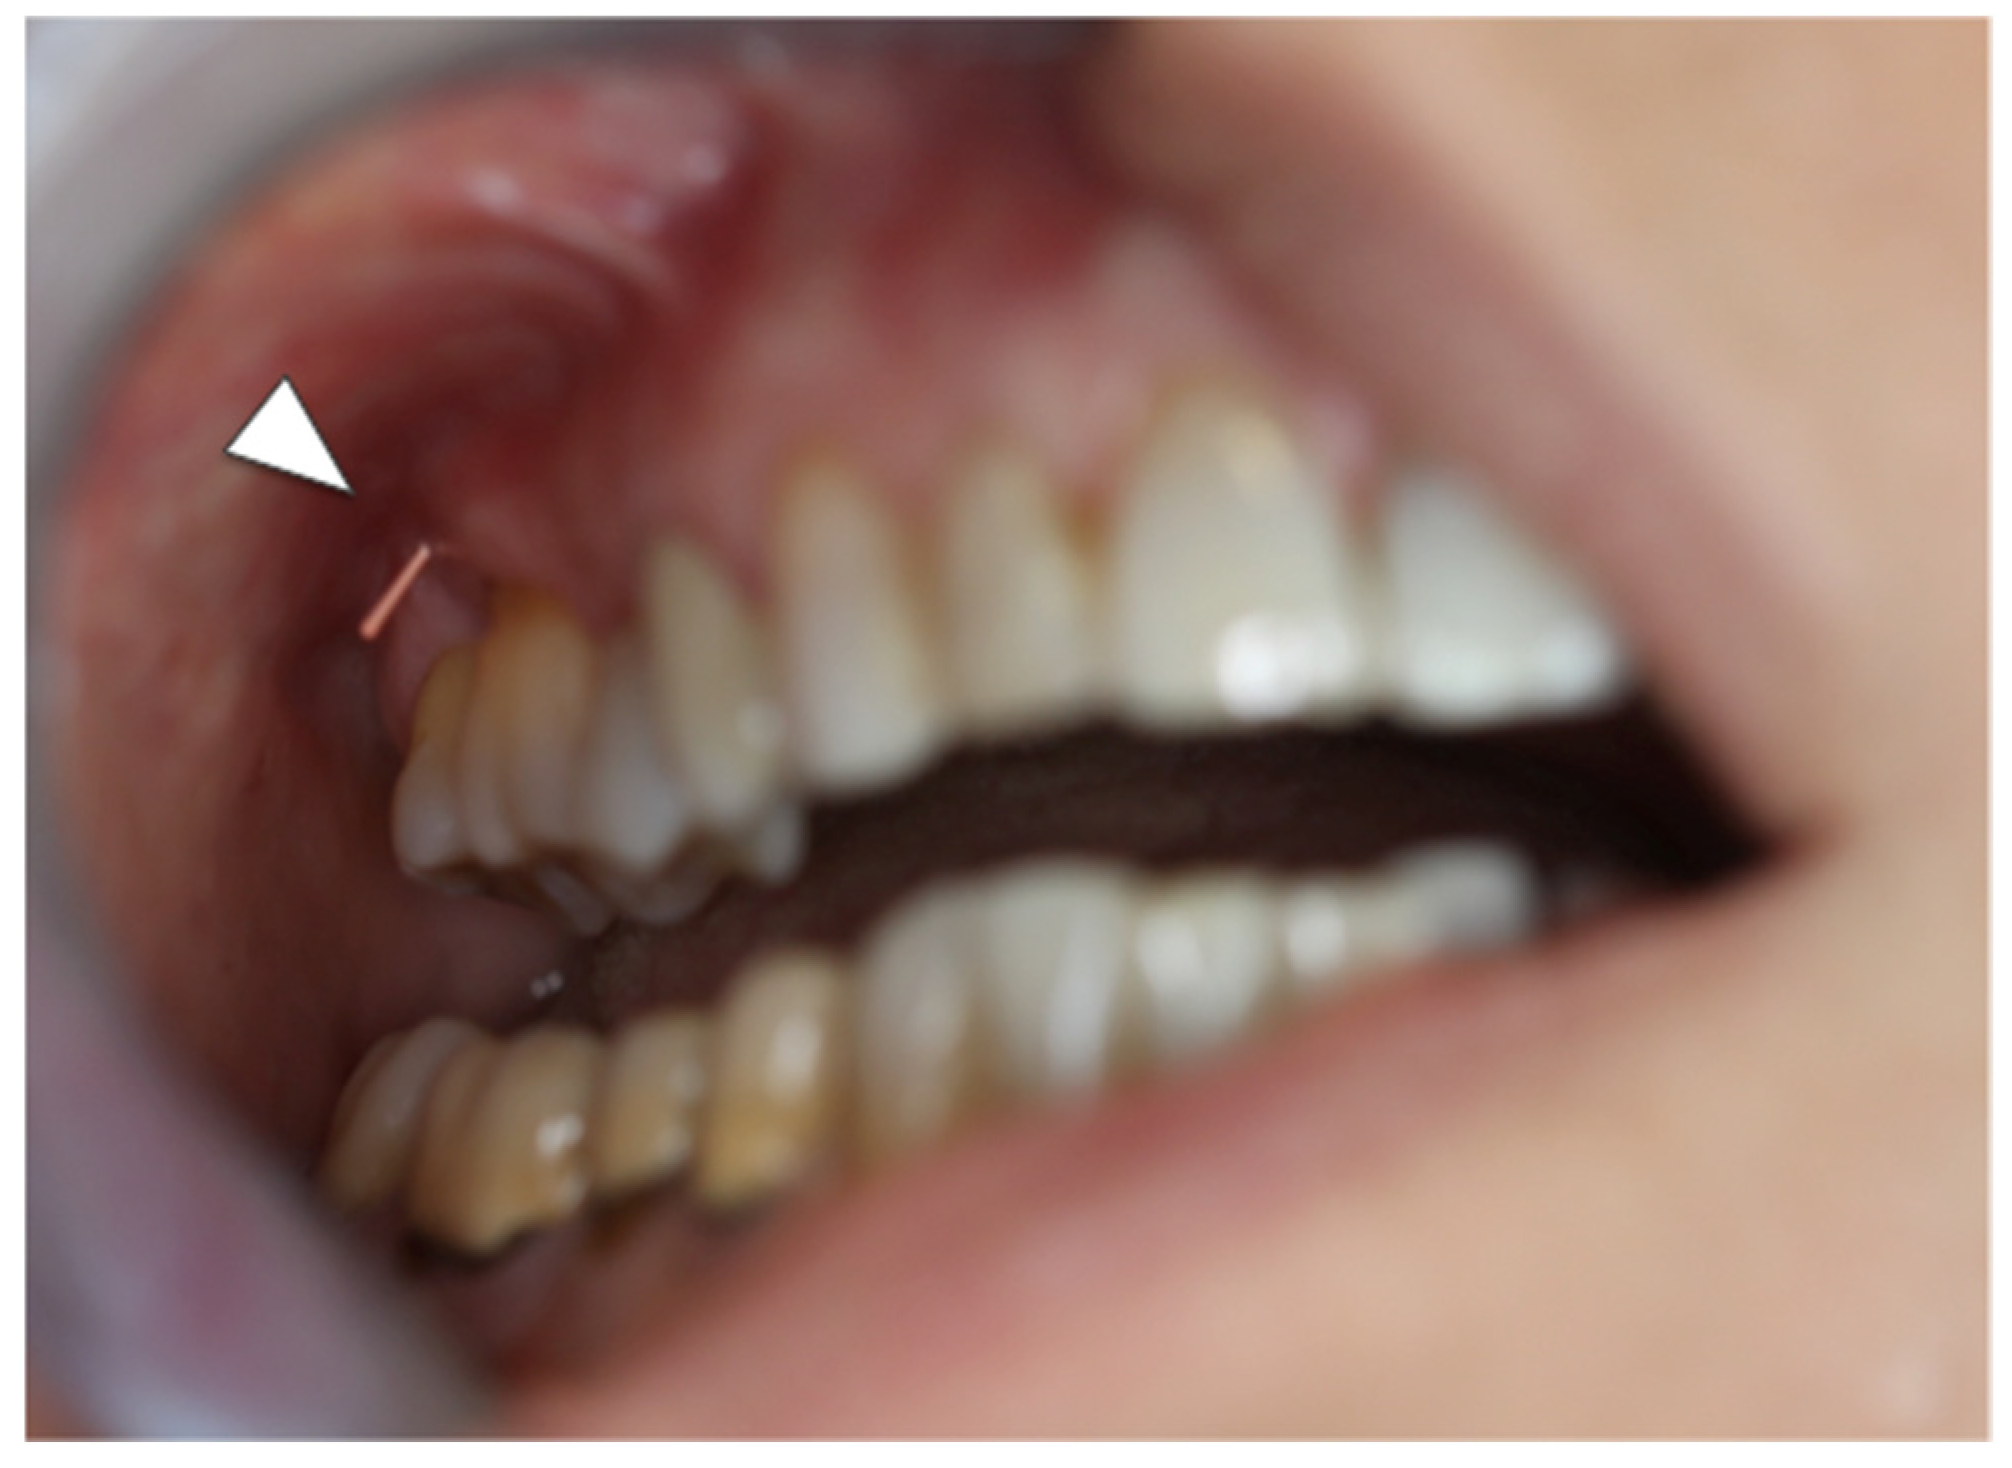

At the first consultation at the outpatient clinic of the Regional Centre for Prevention, Diagnosis and Treatment of Medication and Radiation-related Bone Diseases of the Head and Neck, she presented with a painless probing bone fistula in the site of the previous bone sequestration. Mild inflammation with recession of the surrounding gingiva was observed in the absence of purulent discharge. The first upper right molar was stable without decay or fracture. No other signs were detected in the oral cavity (Figure 1).

Figure 1. Intraoral patient’s image at presentation showing a mucosal fistula in the vestibular buccal sulcus at the upper first right molar with mild gingival inflammation. An endodontic cone was used for dentoalveolar sinus track magnification (white arrowhead).